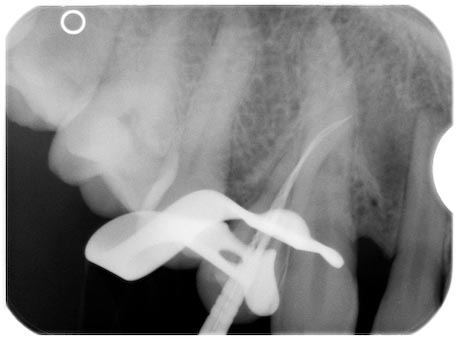

Röntgenmessaufnahme 14

Veröffentlicht 27. März 2009 am 457 × 339 in In die Irre führend – ein nicht alltäglicher Fistelgang